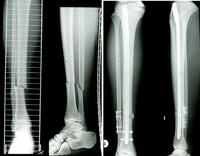

Die Klinik für Unfall- und Handchirurgie am Hegau-Bodensee-Klinikum Singen (Leitung: Chefarzt Dr. med. Steffen Heck) ist durch die Berufsgenossenschaften zur Behandlung Schwerverletzter zugelassen. Unsere besondere Aufmerksamkeit gilt den Verletzungen und Erkrankungen der Hand.

Im Juni 2024 wurden wir bereits zum vierten Mal als Regionales Traumazentrum zertifiziert.